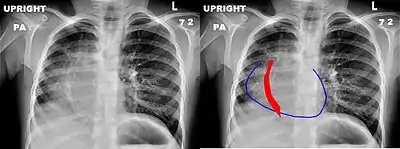

The anomalous venous return forms a curved shadow on chest x-ray such that it resembles a scimitar. This is called the Scimitar Sign. Associated abnormalities include right lung hypoplasia with associated dextroposition of the heart, pulmonary artery hypoplasia and pulmonary sequestration. Incidence is around 1 per 100,000 births.[4]

Chest x-ray of a five-year-old girl with Scimitar syndrome. The heart (blue outline) is shifted into the right half of the chest, and the anomalous pulmonary venous return (red) has a shape reminiscent of a Scimitar.